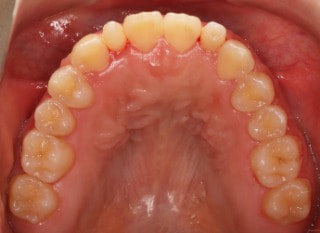

治療後(2年11ヶ月後)